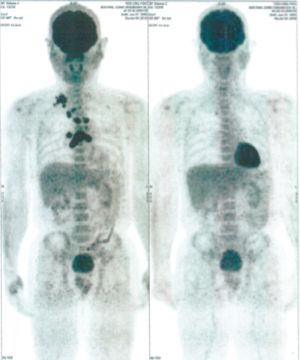

CASE NO: 1 - A FEW MONTHS LATER

A few months after successful treatment for hepatocellular carcinoma, and partially successful for stomach cancer, the PET/CT scan showed the stomach cancer becoming very active, with several metastases to the parts of the liver not previously involved by hepatocellular carcinoma. After a few treatment, all the active stomach cancer lesions in the stomach and in the liver went into remission.